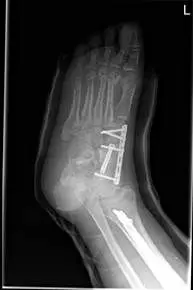

These are pics of an open midfoot fracture and dislocation after a motor vehicle accident.

These are pics of the external fixator on to hold temporary reduction prior to internal fixation

These are pics of the plate and screws stabilizing the fractures after ex fix was removed. An IM rod was also placed for a tibia fracture.